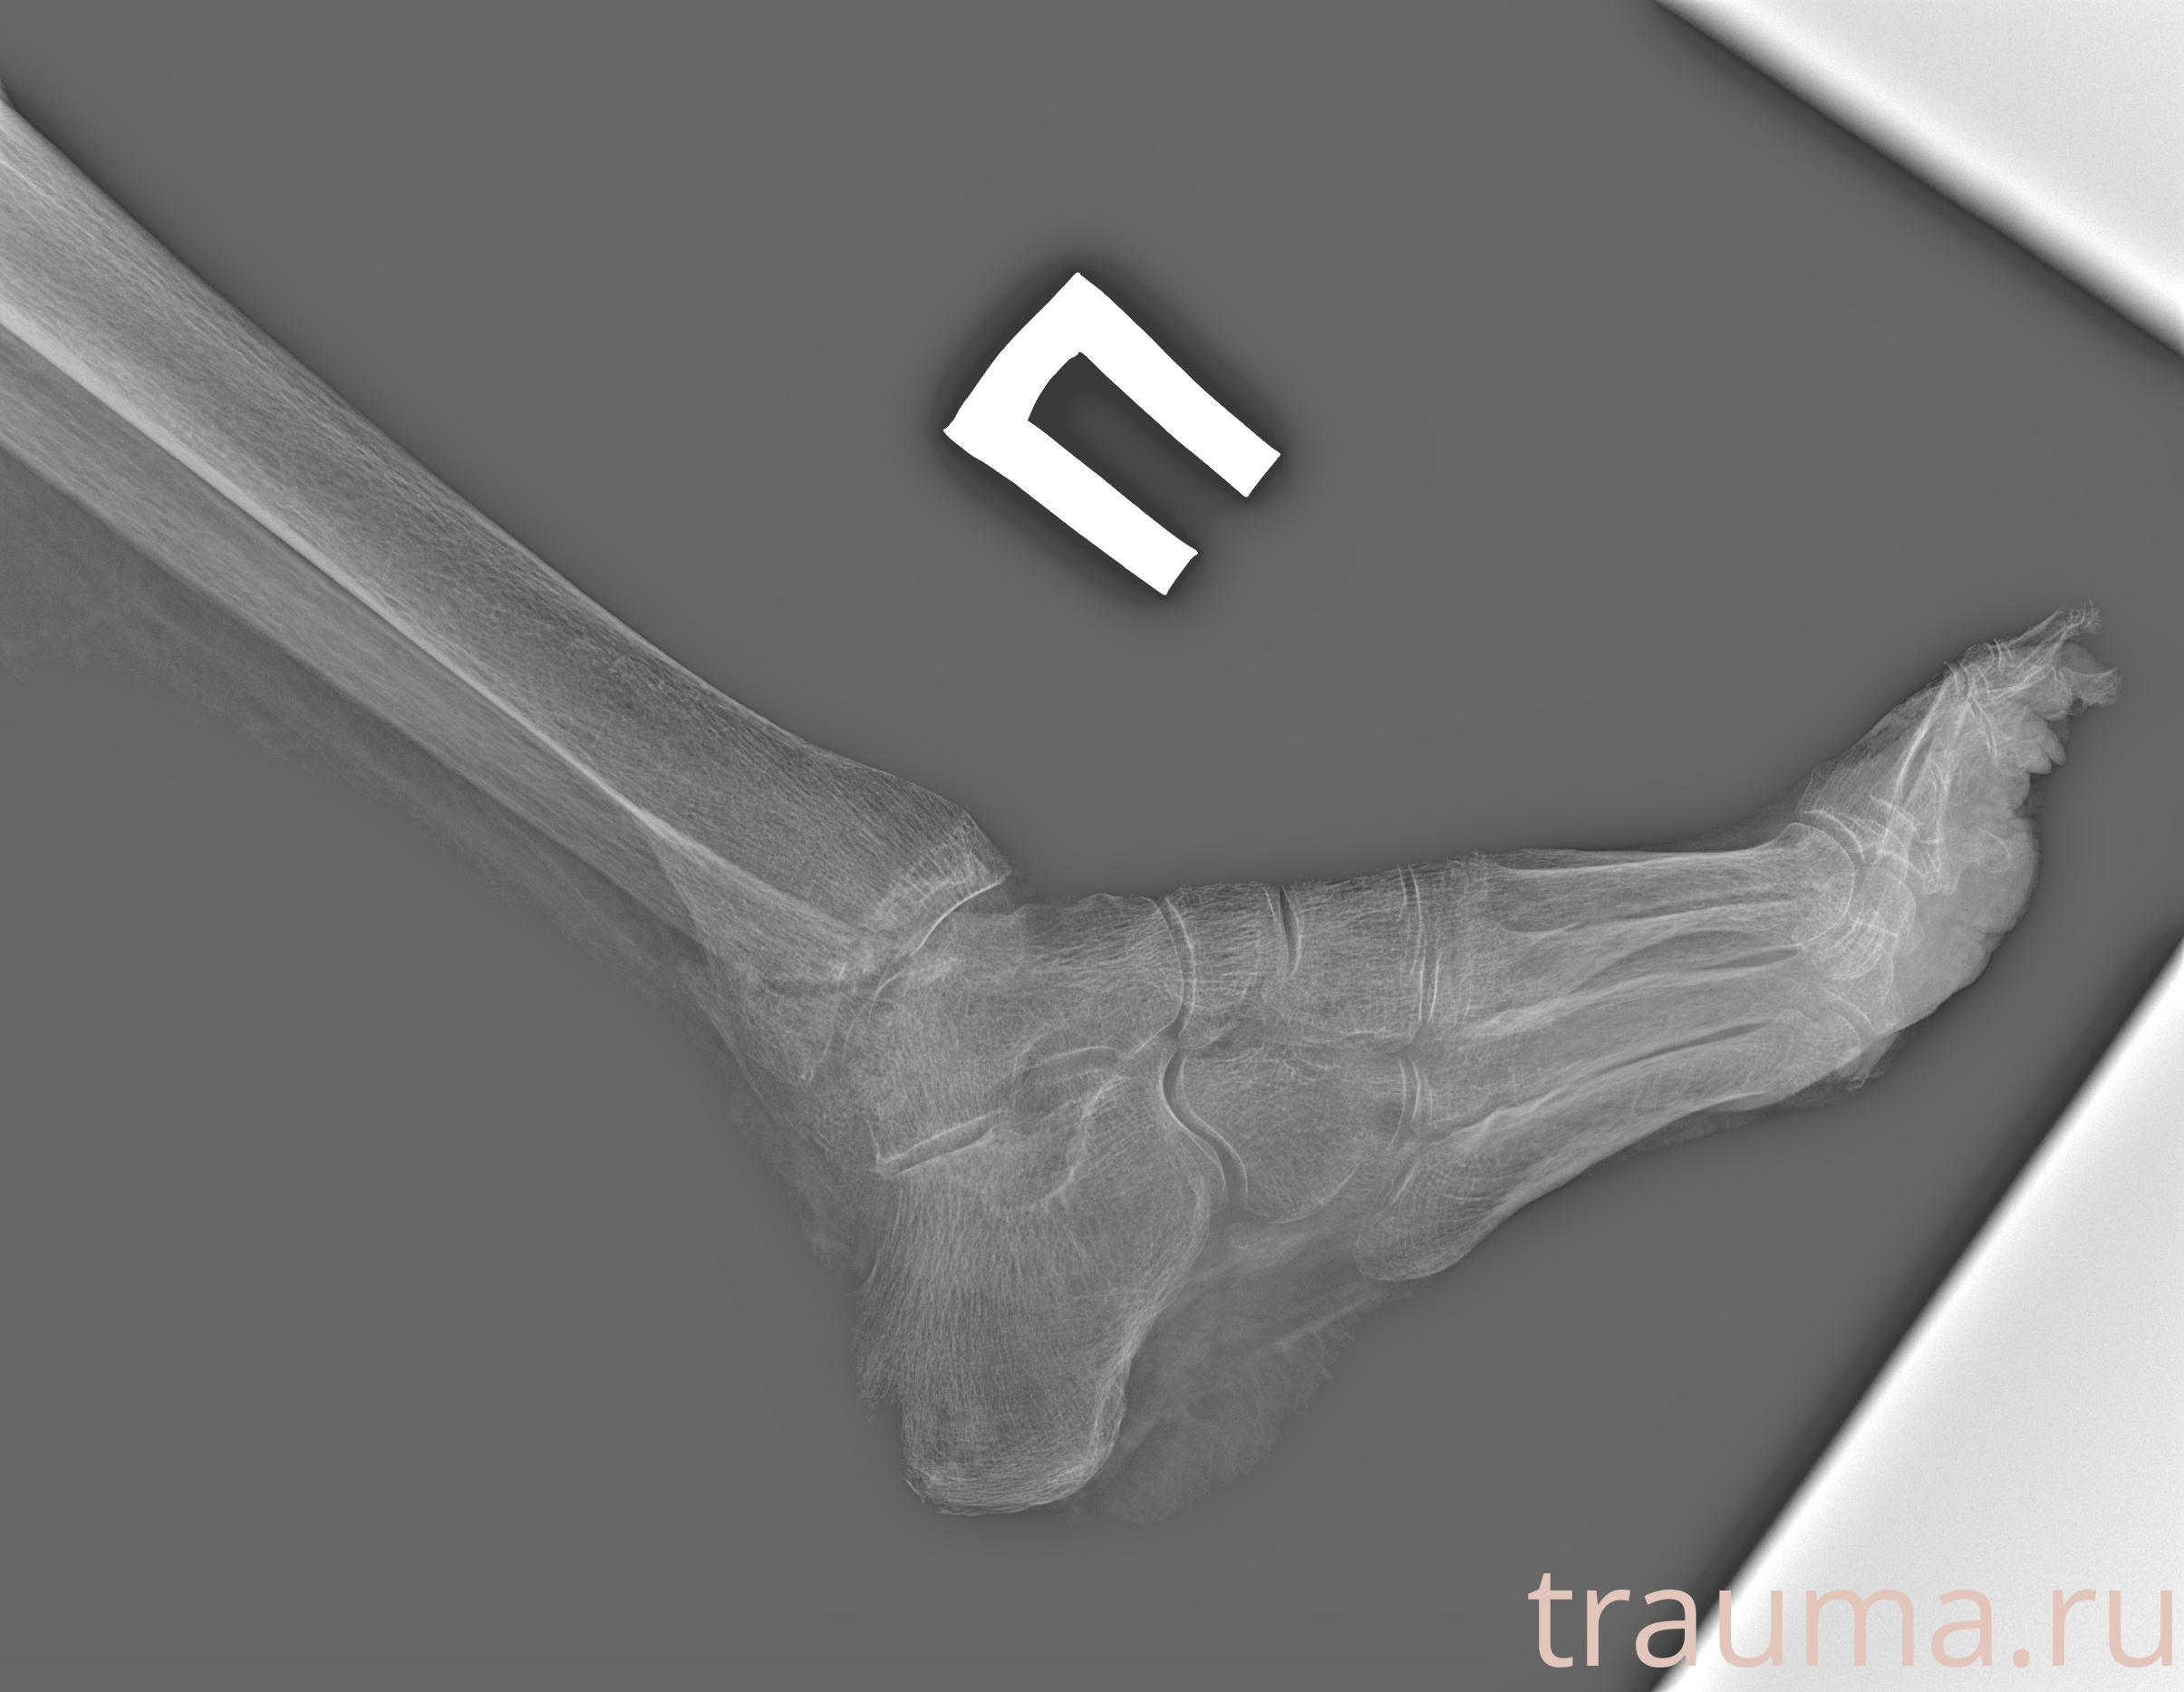

Рентген на дому: по вашему адресу приезжает врач-рентгенолог, травматолог-ортопед с мобильным рентгеновским аппаратом, проводит диагностику травмы или заболевания, делает необходимые рентгенограммы, дает рекомендации по дальнейшему лечению. Получить качественные снимки в домашних условиях возможно благодаря уникальной методике, разработанной МосРентген Центром для института  Склифосовского